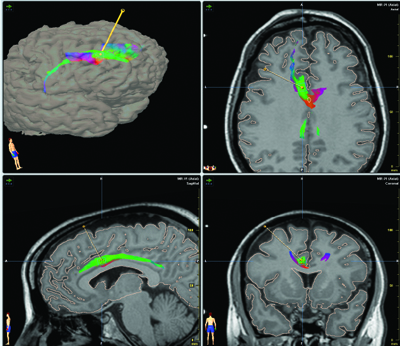

About the targets for deep brain stimulation in treatment resistant depression some options are available:

- The reward circuitry of the ventral striatum and Nucleus Accumbens has been associated with drug addiction and depression for many years. Some case reports showed some partial effect on TRD. One case report with obsessive-compulsive disorder and concomitant major

depression and three cases with TRD. - Subgenual Cingulate Cortex: Area 25. Helen Mayberg found the switch that lifts depression in area 25, a spot deep in the cortex. This area is the key conduit of neural traffic between the thinking frontal cortex or forebrain and the central limbic region that plays a role in emotions and which appeared earlier in our evolutionary development. This area is overactive during depression or sadness. This form of DBS was doen in a Randomized Controlled Trial with 6 patients with overall response of 60%.

- Inferior Thalamic Peduncle. The ITP has proven to be hyperactive in depression, a phenomenon that reverses with effective pharmacological treatment. Successful use of this target in DBS stimulation has been published in one case report. One initial case report indicates promise, large-scale trials of implantation are necessary to determine the efficacy and safety of this target.

- Rostral Cingulate Cortex: Area 24a. No electrode has yet been implanted in the rostral cingulate cortex in humans; however, stereotactic lesioning of this area has shown beneficial effects.

- Lateral Habenula. Only used in animal models with some suggestion that functional inhibition of this area using high-frequency DBS may have therapeutic benefit

These localizations have been described on this blog in another posts: 5 different locations for deep brain stimulation in depression, but now it appears in a peer reviewed article with excelent graphics.

Only three have been tried with patients with TRD or obsessive-compulsive disorder and concomitant major depression. The other anatomical targets are tentative. The most impressive results done with a proper study design was with Broadman area 25 by Helen Mayberg.